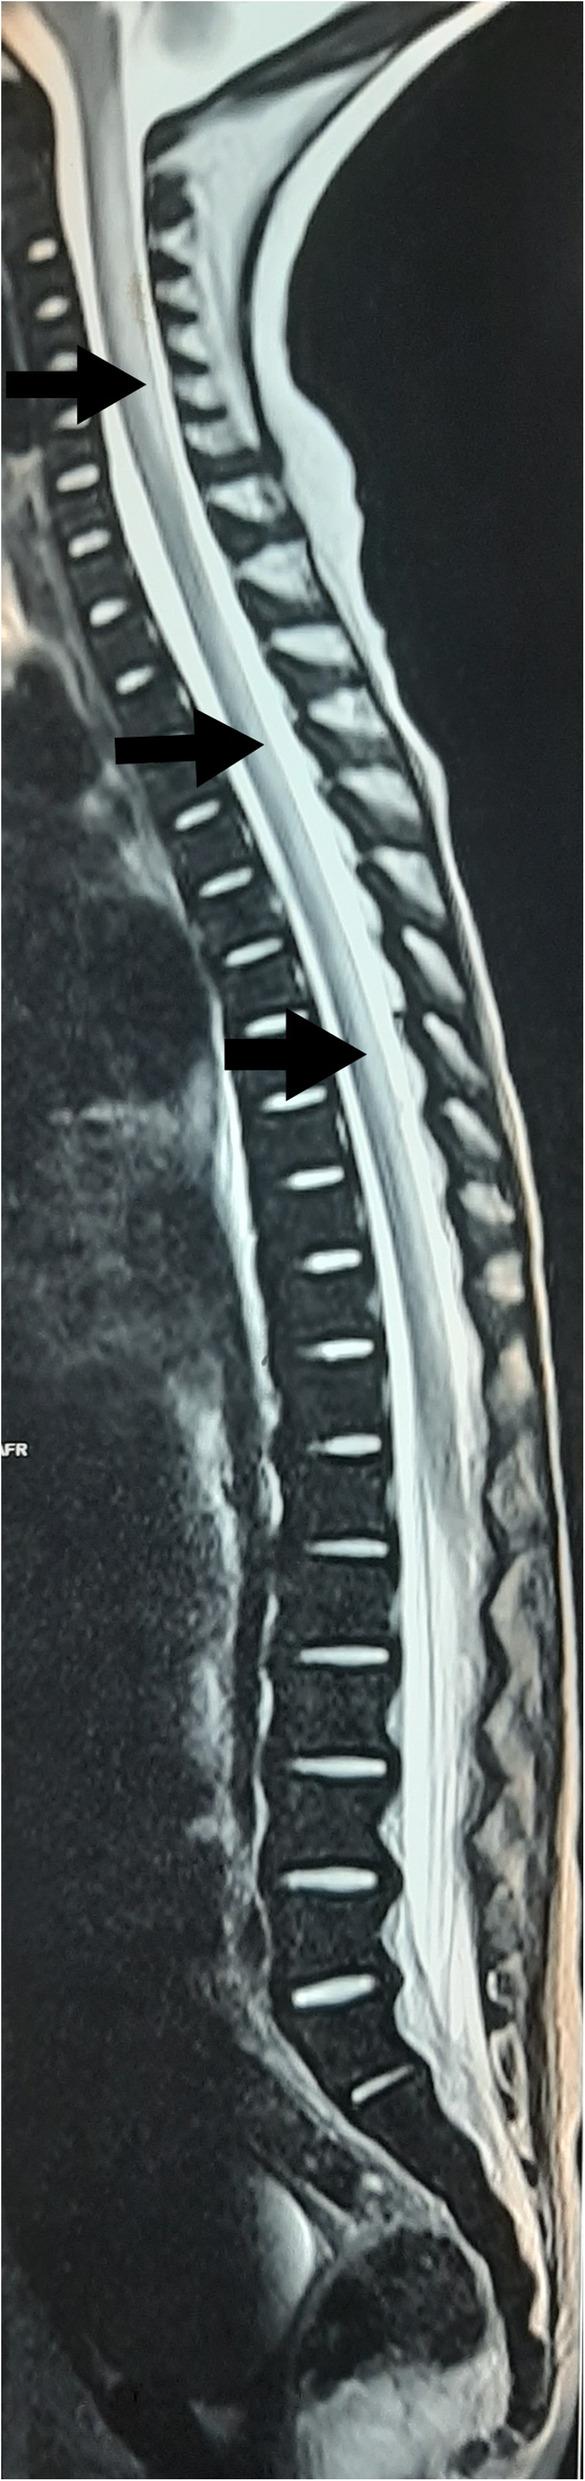

A 4-year old Sri Lankan boy presented with gradually worsening difficulty in walking for two weeks duration. He was previously diagnosed and managed as having non-transfusion-dependent α-thalassaemia based on the presence of hypochromic microcytic anaemia, haemoglobin H inclusion bodies in the blood film and compound heterozygous α-thalassaemia genotype with a gene deletion. However, his transfusion requirement increased over the past three months and he gradually lost his motor developmental milestones during two weeks before admission. The neurological examination revealed generalised hypotonia, exaggerated knee jerks and extensor plantar response. His complete blood count showed pancytopenia, and bone marrow biopsy revealed megaloblastic changes. Serum vitamin B and red blood cell folate levels were low. MRI revealed sub-acute combined degeneration of the spinal cord with characteristic 'inverted V sign'. Urine analysis showed non-nephrotic range proteinuria. The diagnosis of Imerslund-Gräsbeck syndrome was made due to the presence of non-nutritional vitamin B deficiency and asymptomatic proteinuria. He showed a rapid haematological and neurological improvement to intramuscular hydroxocobalamin.

一名4岁的斯里兰卡男孩出现行走困难逐渐加重,持续两周。他之前因存在低色素小细胞贫血、血片中的血红蛋白H包涵体以及具有基因缺失的复合杂合α地中海贫血基因型,被诊断为非输血依赖型α地中海贫血并接受相应治疗。然而,在过去三个月里他的输血需求增加,且在入院前两周逐渐失去运动发育里程碑。神经系统检查显示全身肌张力减退、膝反射亢进和伸性跖反射。他的全血细胞计数显示全血细胞减少,骨髓活检显示巨幼细胞改变。血清维生素B和红细胞叶酸水平较低。MRI显示脊髓亚急性联合变性,具有特征性的“倒V征”。尿液分析显示非肾病范围蛋白尿。由于存在非营养性维生素B缺乏和无症状蛋白尿,诊断为伊默斯伦德 - 格里斯贝克综合征。他对肌肉注射羟钴胺素表现出快速的血液学和神经学改善。